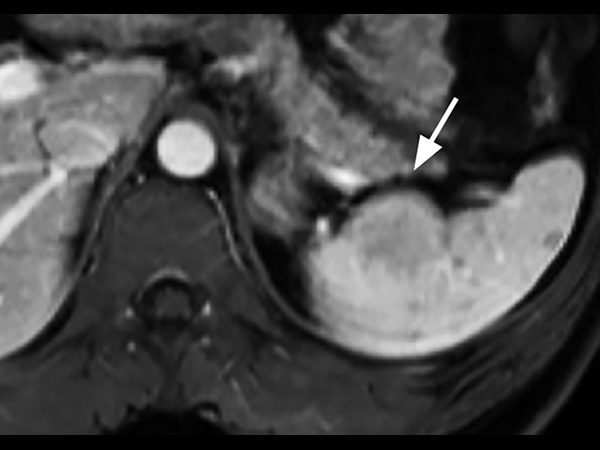

A 33-year-old male with history of non-Hodgkin lymphoma undergoes an MRI exam on Ingenia 1.5T to visualize clinically suspected recurrent disease. Whole-Body MRI was performed using T1W TSE and STIR imaging (4 stations, matrix 400x400, 6 mm slices). Additional whole-body diffusion imaging (3 stations, matrix 192x192, 6 mm slices) with MIP unmasks a focal area of diffusion restriction in the left scapular region. Subsequent contrast-enhanced 3D mDIXON imaging reveals a bone manifestation of a lesion in the left scapular angle. Furthermore, multifocal splenic infiltration is depicted. Note that the splenic lesions are veiled by the high physiological background diffusion signal in splenic tissue. The findings are compatible with skeletal and splenic tumor recurrence of non-Hodgkin lymphoma. Further total body follow-up imaging according to therapeutic regime is advised. Whole-body MRI allows rapid visualization of lesions in this lymphoma patient. A finding of multifocal organ manifestations has a decisive impact on further patient management and therapeutic regime. The fully digital Ingenia 1.5T MR system allows for rapid whole-body MRI with homogenously high imaging quality in depicting these lesions. Additionally, state-of-the art techniques such as whole body DWI can be included in the exam protocol, which further enhances the capability for visualizing lesions in oncology patients.

T1w mDIXON-FFE